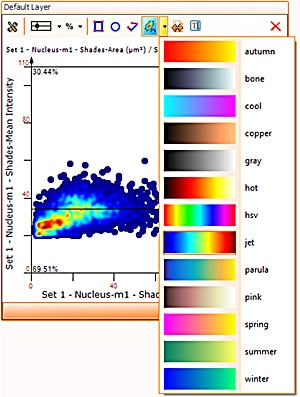

Finally, HistoQuest has a heatmap feature in scattergrams.

This feature will show areas of objects density in the scattergram which may not be visible in highly populated scattergrams and so deliver more information when working with them.